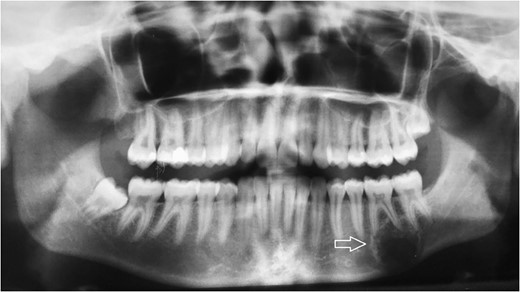

Follow-up panoramic X-ray imaging at 12 months after initial diagnosis showing no significant progression of the tumor lesion.